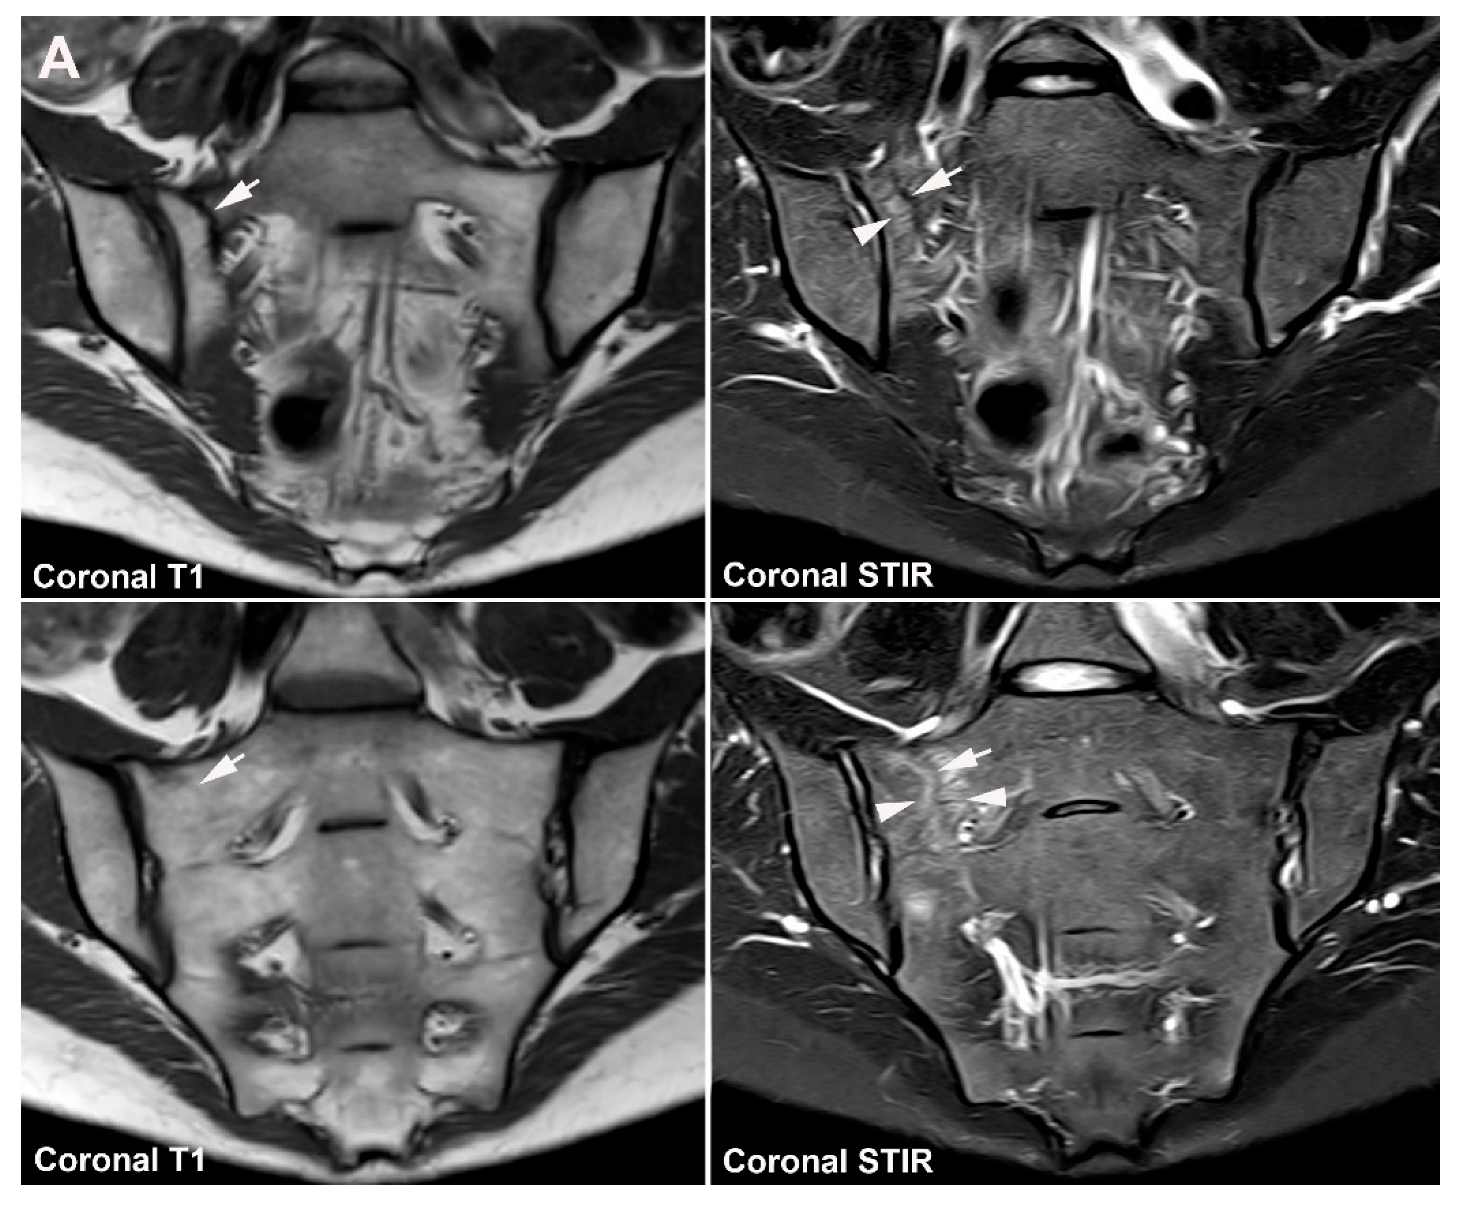

5.1. Osteitis Condensans ilii (OCI)

5.2. Pregnancy-Related Changes